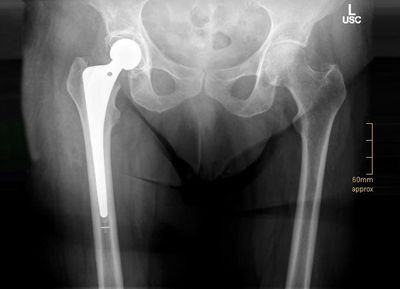

Unsere Klinik ist zusammen mit dem Zentrum für Alterstraumatologie auf die Therapie und Betreuung älterer Menschen ausgerichtet. Aufgrund unserer Expertise behandeln wir daher auch Patienten, die nicht notfalloperiert werden müssen. Also zum Beispiel, wenn diese einen künstlichen Gelenkersatz an Hüfte oder Knie benötigen.